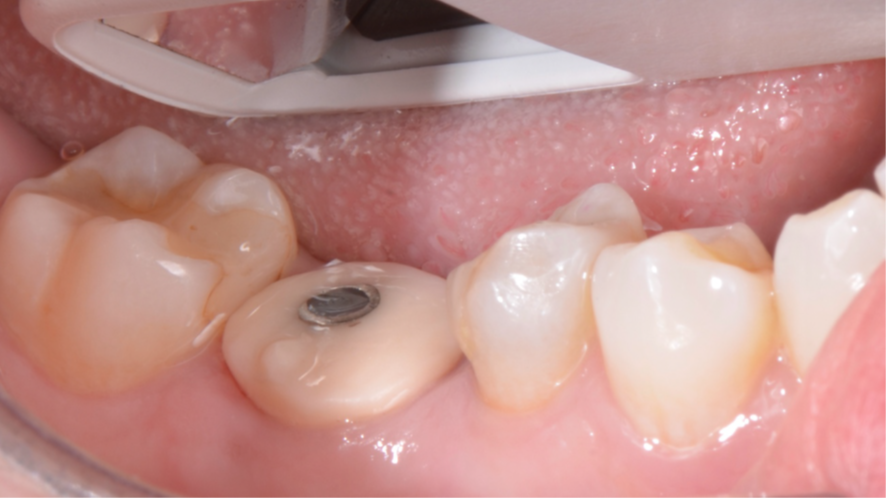

Mulher de 48 anos, sem antecedentes médicos relevantes, procurou atendimento odontológico com queixa principal de dor contínua em região do primeiro molar inferior direito. Na avaliação clínica foi observado uma fístula na vestibular do dente 46 (Figura 1) e a tomografia revelou uma fratura longitudinal, comprometendo a manutenção deste dente (Figura 2). Confirmada a necessidade de exodontia, foi planejada a instalação de um implante imediato e a confecção de um cicatrizador personalizado diretamente na plataforma do implante com um pilar provisório de titânio. Foi realizada uma extração dentária minimamente traumática visando preservar a integridade dos tecidos moles e duros circundantes (Figuras 3 e 4).

Após a instalação do implante, um cicatrizador foi colocado somente para proteger a conexão morse do implante e o GAP foi preenchido com Extra Graft 1g (Figura 7). Como foi alcançada uma alta estabilidade primária, um pilar provisório de titânio foi instalado e nele foi confeccionado um cicatrizador personalizado com resina fluida (Figuras 8, 9 e 10).